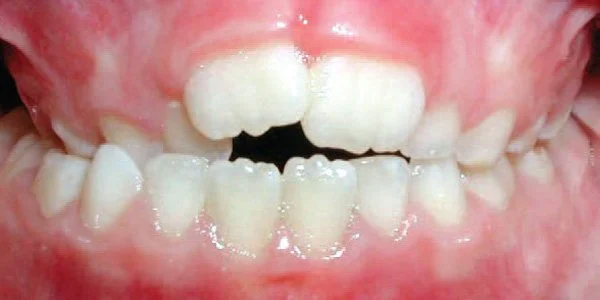

Openbite

Front teeth do not meet when teeth are closed.